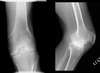

45

Name 4 major radiographic features on this radiograph.

- generalized osteopenia - widening of intercondylar notch - uniform jt space loss - ballooning of epiphysis

46

Give 2 differentials in order of likelihood. What 2 features support your diagnosis?

1. Hemophilia 2. JIA - ballooning of epiphysis - squaring of patella